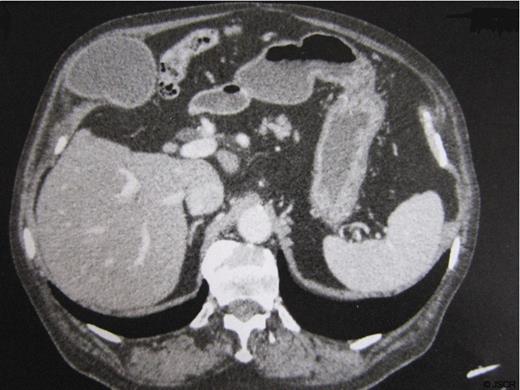

The patient was an 85 year-old man with history of hypertension, previous surgery for perforated diverticular disease (Hartmann procedure followed by reversal of colostomy). He had suffered from occasional pain in the right upper quadrant for several months. The physical examination showed a 5 cm mass in the right upper quadrant tender to palpation. Ultrasound and CT confirmed the presence of a lithiasic gallbladder herniated through the abdominal wall (fig.1), with a dilatation of the common bile duct that measured 11 mm, due to a 17 mm obstructive infundibular stone as it happens in Mirizzi syndrome type I (fig.2).

Another interesting aspect of this case is the presence of a chronically distended gallbladder (gallbladder hydrops), associated with extrinsic compression of the common hepatic duct by an impacted stone in the infundibulum (Mirizzi syndrome type I) (8). It is probably the gallbladder dilatation that plays an important role in the development of the hernia pressing constantly the gallbladder against the abdominal wall. Usually the clinical picture is represented by a right upper quadrant pain, associated with variable degrees of a compromised general condition. In our experience the preoperative study based on computed tomography is essential for the diagnosis of the gallbladder hernia, and it provides also additional information on the abdominal wall defect.